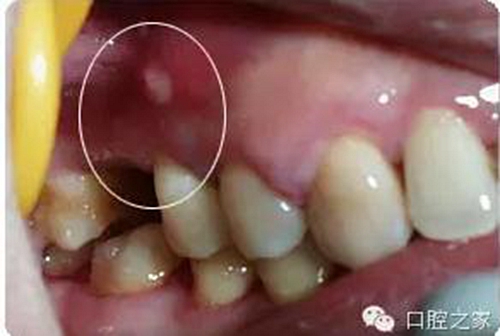

(3)根管壁側(cè)穿 手用擴大針作根管清理或擴大,較少出現(xiàn)側(cè)穿現(xiàn)象,除非是用大號擴大針作強行擴大。采用機用擴大針或樁冠修復(fù)時進行釘?shù)乐苽?,如操作不慎較易側(cè)穿。側(cè)穿后如未發(fā)現(xiàn)或處置不當(dāng),日后可出現(xiàn)有竇道的慢性根尖周炎。

根管內(nèi)因素治療失敗,查清原因后重新治療,大都可以治愈。根管外因素所致失敗,除部分病例配合外科可以治愈,大多數(shù)病例重新作根管治療也難以成功,形成真正的難治性根尖周炎。筆者在《實用牙髓病診療學(xué)》中將竇道口形狀分為6種,其中的膿性針眼狀竇口(壓有白色膿液溢出,竇口僅有針眼大小無突起)幾乎都是根管外原因,單純根管治療難以奏效。